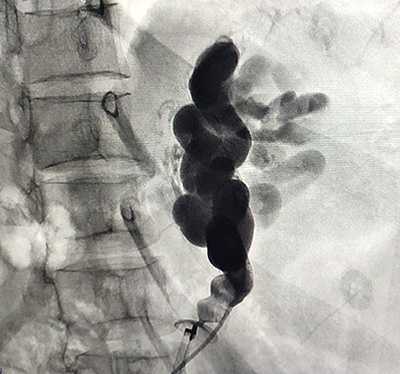

We will then perform a venography, which is a type of imaging technique in which X-rays are used to see the vessels clearly. This will allow us to confirm exactly which vessels need to be treated and if there are any other abnormal or dilated vessels which have not previously been identified. A medication will then be injected into the dilated abnormal venous channels through the catheter, until they are completely filled. Finally, the balloon will be deflated and we withdraw the catheter in cases of BRTO and in cases of PARTO Vascular Plug is permanently deployed in the shunt.

Recent reports have stated that BRTO/PARTO is a less invasive and more effective way to manage gastric varices than shunt surgery or TIPS. BRTO/PARTO can in most cases completely obliterate these abnormal bleeding venous channels. One of the greatest advantages of BRTO is its preservation of liver function. Moreover, the increase of blood flow in BRTO can also improve liver function in cases where the patient has cirrhosis (scarring of the liver).